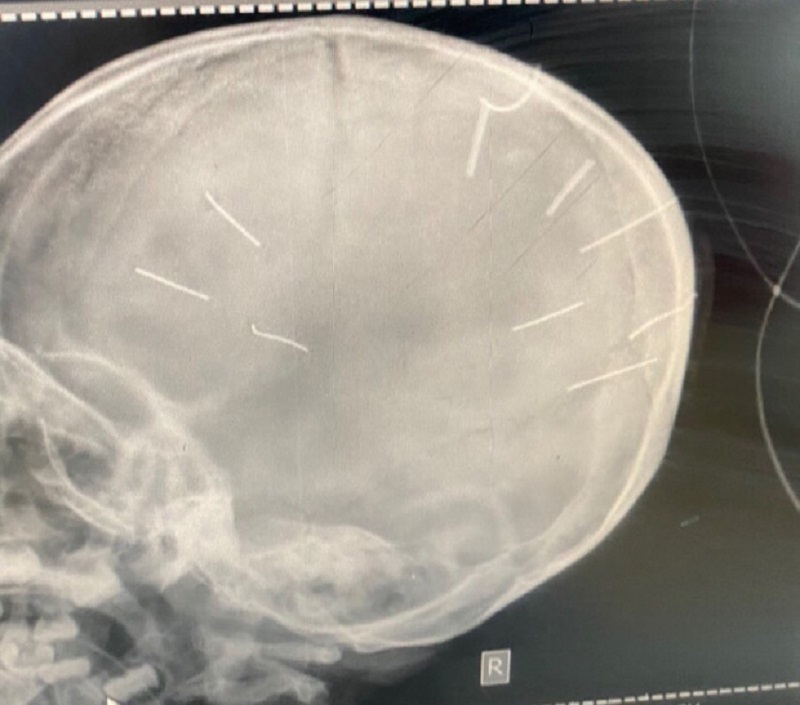

| Hình chụp cắt lớp phát hiện hình ảnh giống đinh trong sọ |

Ngay sau đó, các bác sĩ khoa cấp cứu đã chụp phim, làm chẩn đoán và phát hiện 9 dị vật giống đinh trong sọ não bé gái nên đã chuyển tuyến lên Bệnh viện đa khoa Xanh Pôn, đồng thời báo Công an huyện Thạch Thất.

Sau khi Bệnh viện Đa khoa Xanh Pôn tiến hành chụp cắt lớp, dựng hình đã nhận thấy có những hình ảnh giống như đinh gỗ ở sọ và tổ chức não của bé Đ.N.A.